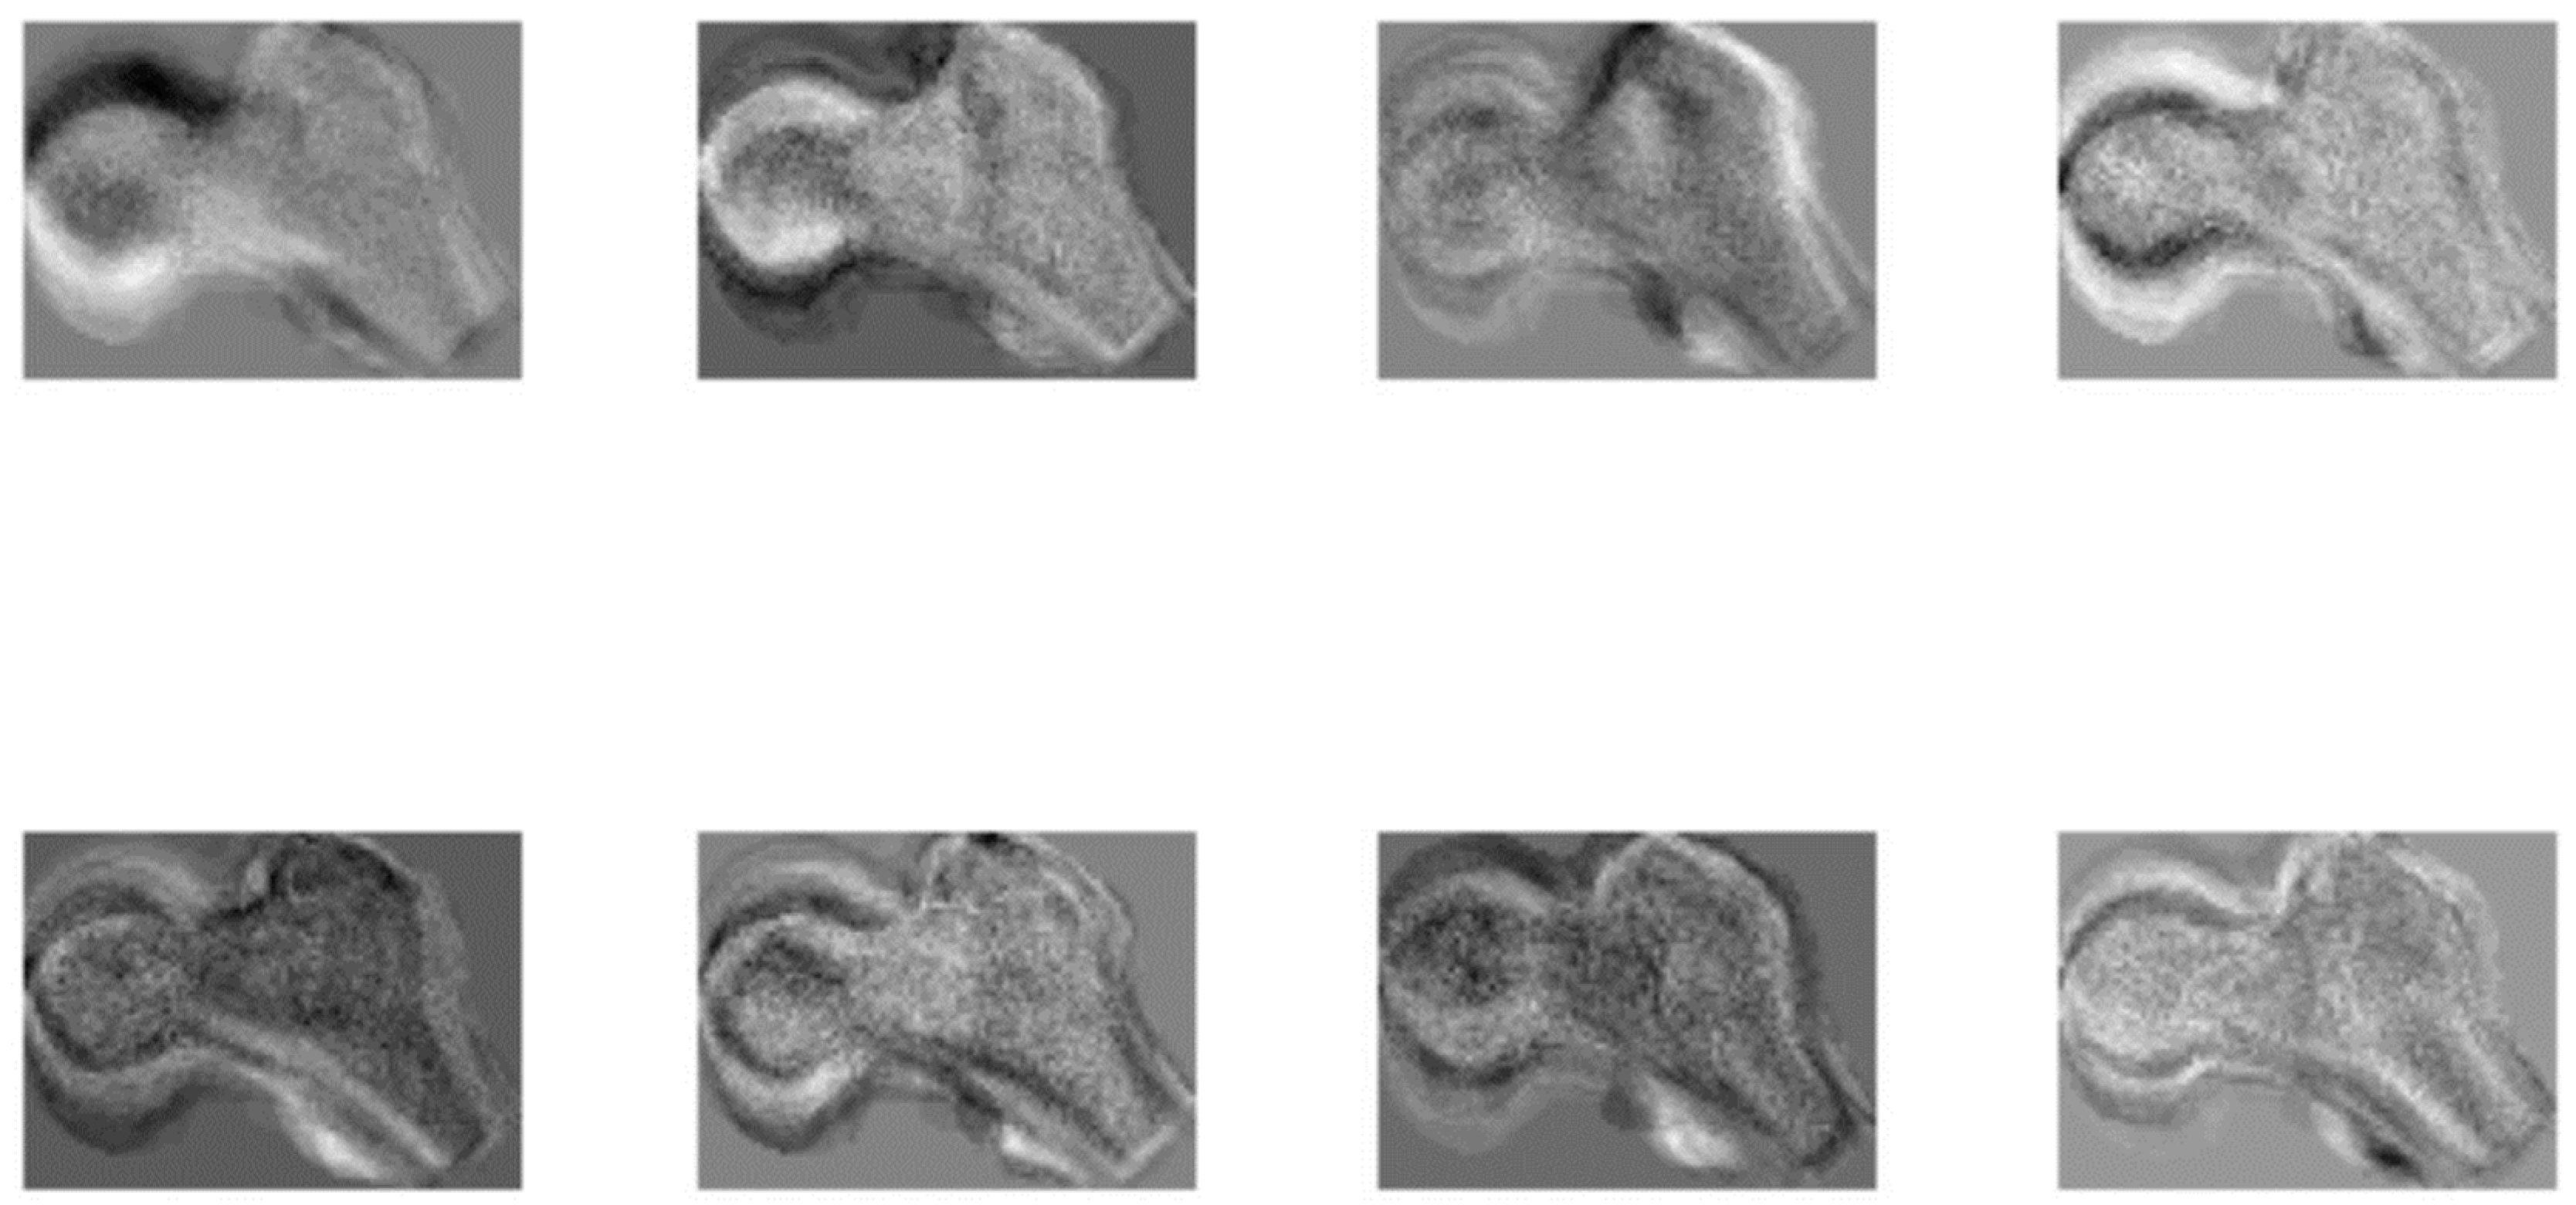

2.2.2. Age Estimation from the Femora Space with K-Nearest Neighbor Search